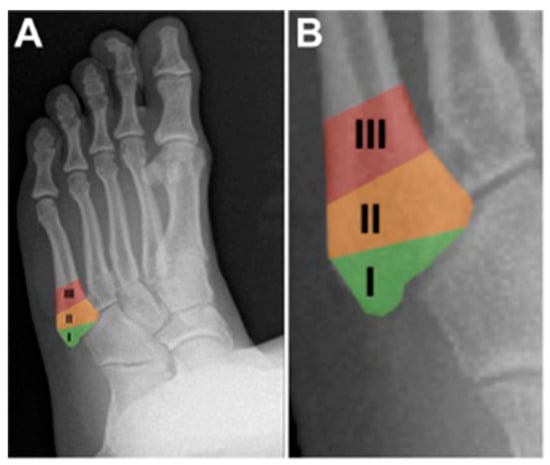

3.1. Classification

3.2. Diagnosis